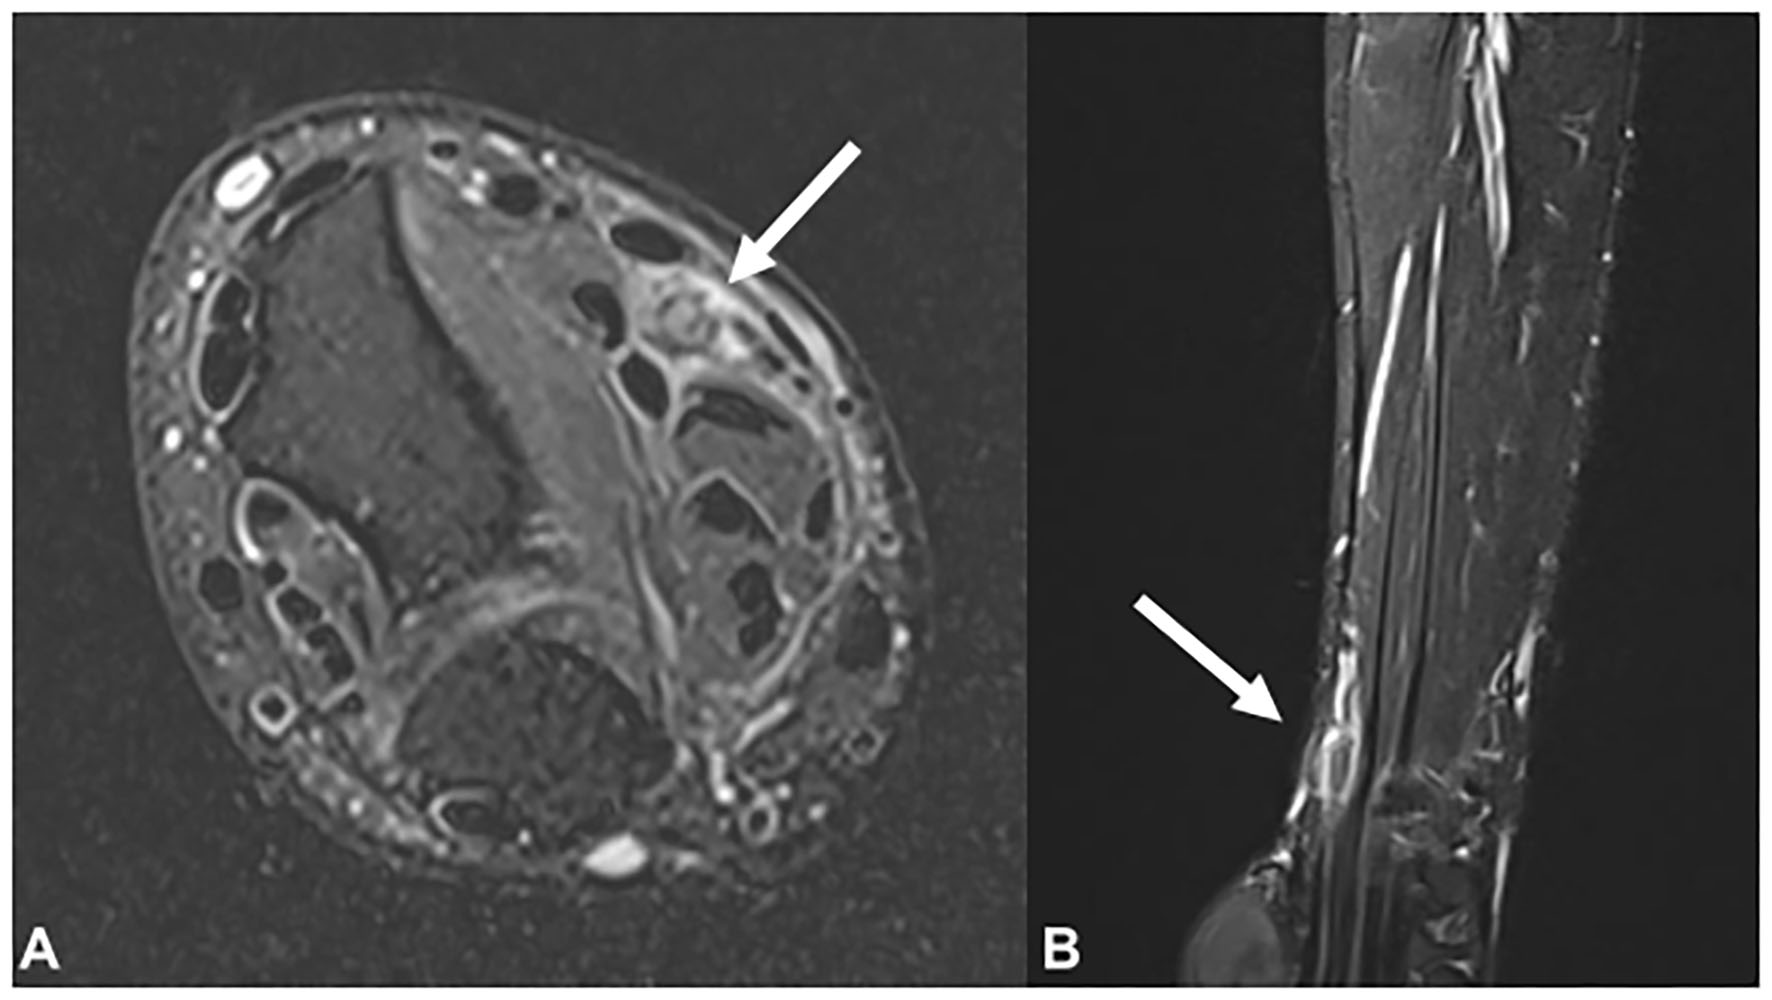

Plain radiographs showed no signs of fracture or other abnormalities. Ultrasound examination revealed a hypoechoic, swollen right median nerve, 4 cm proximal to the wrist crease. The cross-sectional area (CSA) of the right median nerve at the lesion site was 0.19 cm2, while that of the left median nerve was 0.09 cm2 (Figure 1). Magnetic resonance imaging (MRI) of the right forearm revealed edema in the surrounding fat tissue and a focal defect in the epineurium of the right median nerve, at the distal radius level (Figure 2).

Figure 2. Magnetic resonance imaging findings of the right median nerve (arrow) in the (A) T2-weighted axial view and (B) T2-weighted sagittal view. Focal thickening and signal change in the right median nerve is observed at the distal radius level.